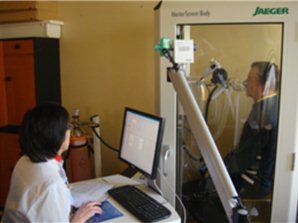

Как уже было сказано выше, легкие – это главный орган, на который воздействует саркоидоз. Лечение легких затрудненно по причине того, что в 90% случаев заболевание протекает абсолютно без каких бы то ни было выраженных симптомов. В подобных ситуациях саркоидоз можно выявить только при рентгенологическом исследовании. Отсутствие симптомов объясняется поражением внутрилегочных лимфаузлов, что в подавляющем большинстве случаев можно определить только с помощью специальной аппаратуры, так как у больных не наблюдается никаких внешних проявлений.

Диагностика и лечение саркоидоза

Состояние легочных тканей и распространение воспаления контролируются с помощью регулярных рентгенологических исследований.